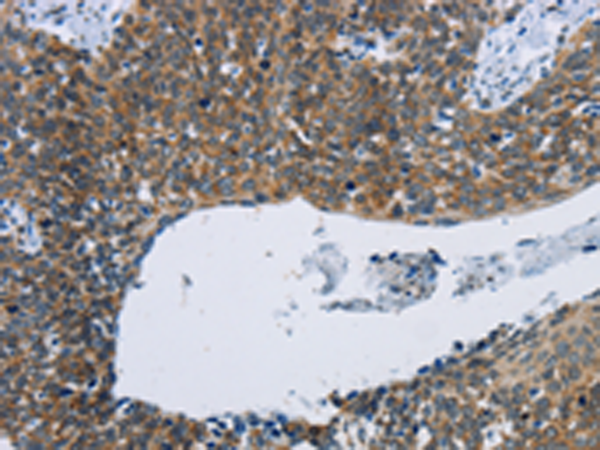

分类: 科研抗体货号: P04922别名: PBF; PRF1; HDBP2; PRF-1; HDBP-2; HDRF-2; Si-1-8-14应用: IHC反应种属: Human